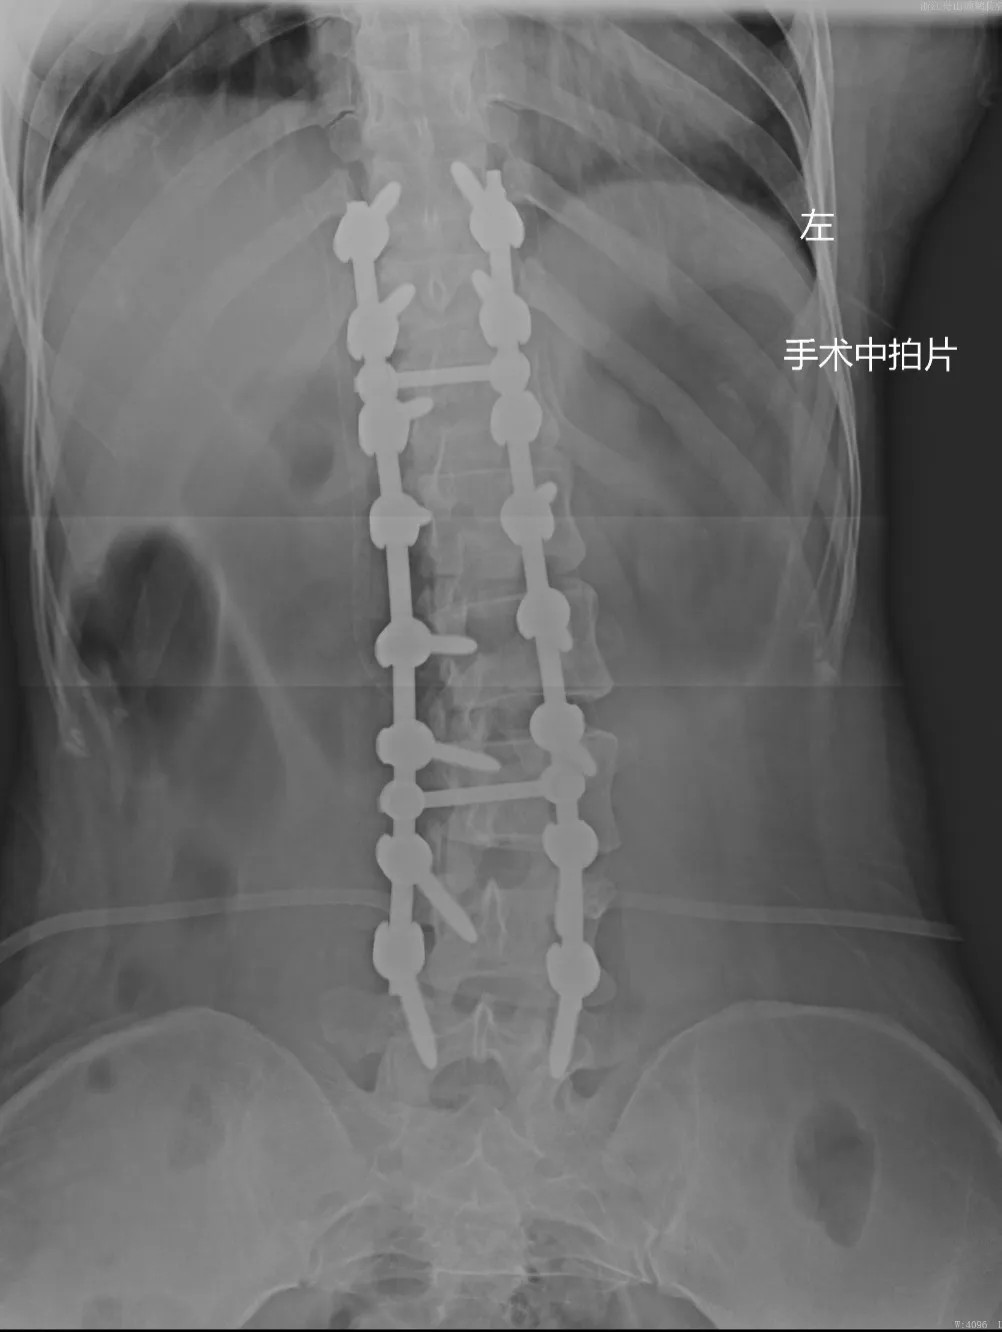

在充分的術(shù)前準(zhǔn)備后,脊柱科、微創(chuàng)治療中心專家團(tuán)隊(duì)為文女士(化名)進(jìn)行了脊柱側(cè)彎矯形、植骨融合內(nèi)固定術(shù),歷經(jīng)近4個(gè)半小時(shí)的精細(xì)操作,手術(shù)圓滿完成。術(shù)中全程使用術(shù)中電生理監(jiān)測(cè)系統(tǒng),每步都力求精準(zhǔn)細(xì)致。

近日,文女士(化名)來院復(fù)診,整體恢復(fù)良好,術(shù)前活動(dòng)不便的癥狀明顯好多了,腰背部肌肉也恢復(fù)了一些,脊柱生理曲度相比術(shù)前有所恢復(fù),側(cè)彎癥狀也明顯改善,下胸椎、腰椎向左側(cè)側(cè)凸畸形較前改善,腰背部轉(zhuǎn)側(cè)活動(dòng)不利較前改善。